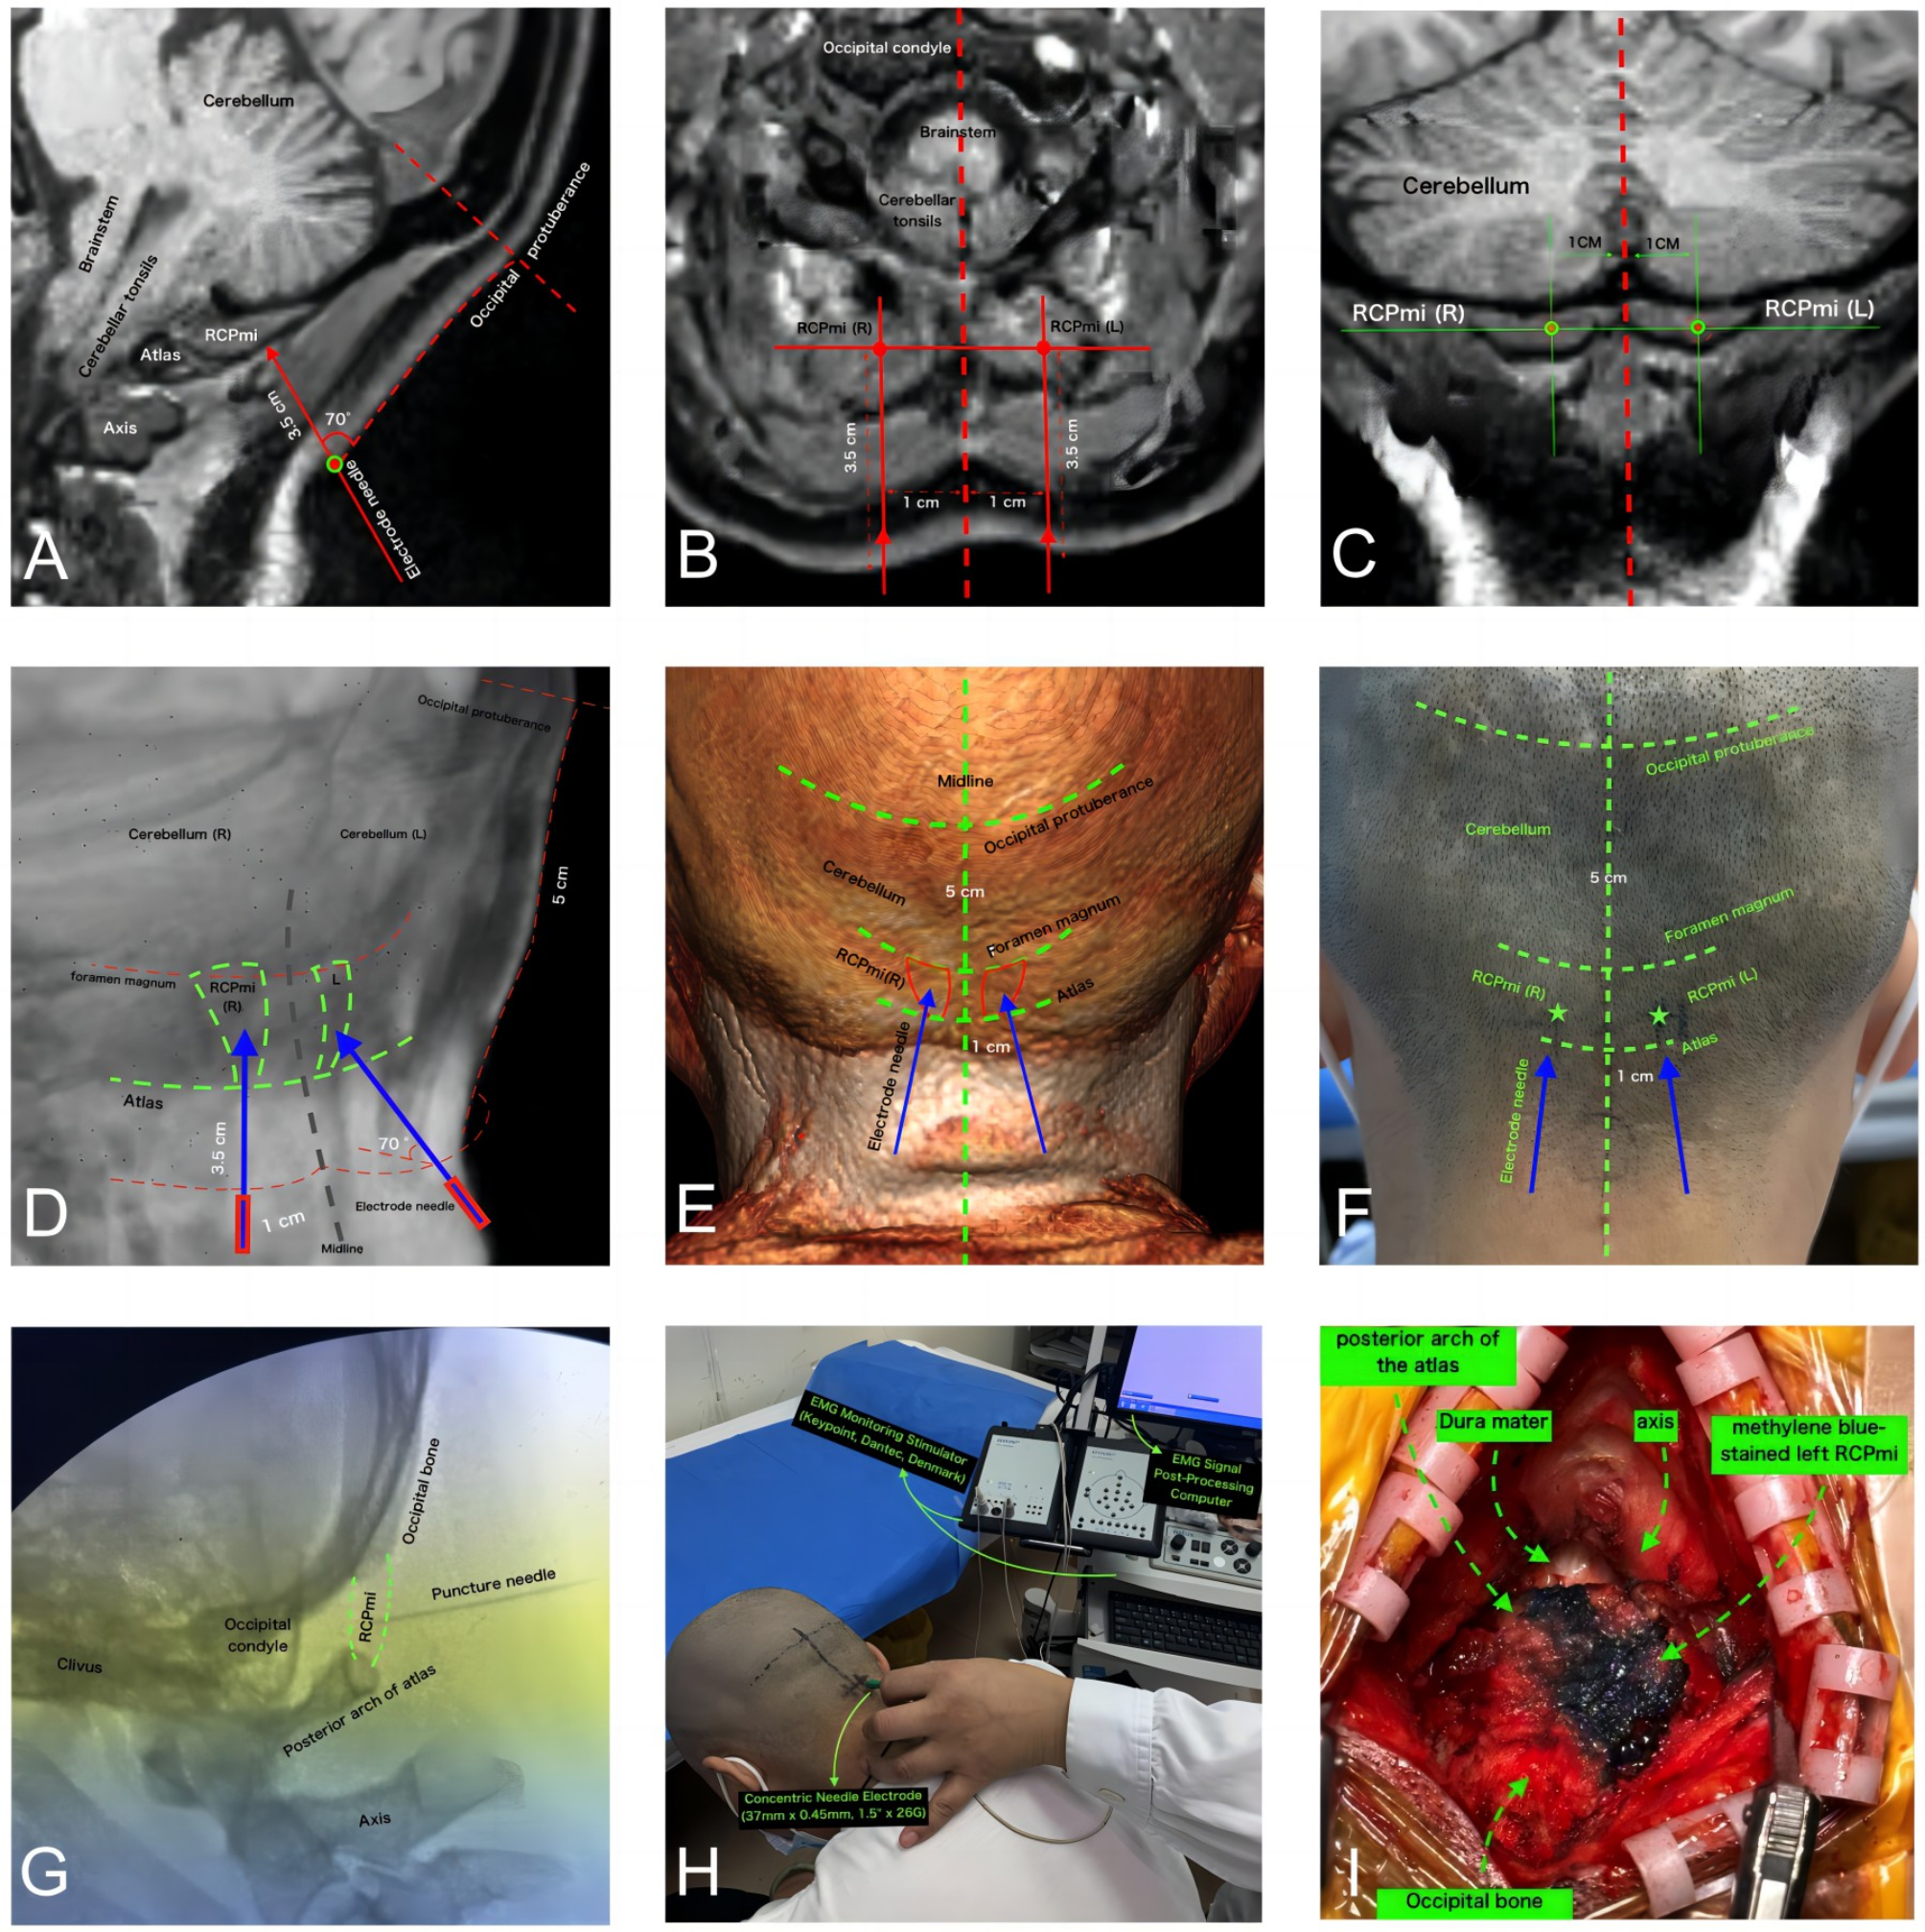

Fig. 1

Reference diagram for nEMG puncture localization of RCPmi. (A) Pre-puncture, head and neck 3D-T1 sequence, sagittal view near midline RCPmi localization slice. (B) Pre-puncture, head and neck 3D-T1 sequence, axial view RCPmi localization slice. (C) Pre-puncture, head and neck 3D-T1 sequence, coronal view RCPmi localization slice. (D) Pre-puncture, head and neck 3D-T1 sequence, 3D perspective reconstruction localization slice. (E) Pre-puncture, head and neck 3D-T1 sequence, 3D body surface reconstruction localization slice. (F) Localization diagram of RCPmi puncture site on the subject. (G) Intraoperative C-arm X-ray sagittal localization diagram during puncture. (H) Patient condition during nEMG testing. (I) Preoperative nEMG examination puncture using methylene blue to stain RCPmi, immediately followed by posterior cranial fossa decompression surgery to verify puncture accuracy. Results show that the deep blue part is the left side RCPmi, accurately punctured. RCPmi rectus capitis posterior minor, EMG electromyogram.